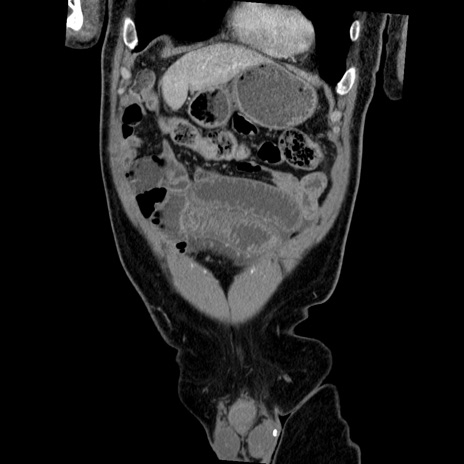

症例22(冠状断像)

【症例】50歳代男性

【主訴】腹痛

【現病歴】AVMからの被殻出血のため回復期リハ病棟入院中。 本日午後3時頃急に下腹部痛が出現した。

【既往歴】AVM、被殻出血、虫垂炎、高血圧

【身体所見】意識晴明、左半身不全麻痺、会話の理解は良好、36.5°C、腹部:膨隆、全体に板状硬、下腹部正中に圧痛点あり、反跳痛-、筋性防御不明、右下腹部にope scar

【データ】WBC 9400、CRP 0.06